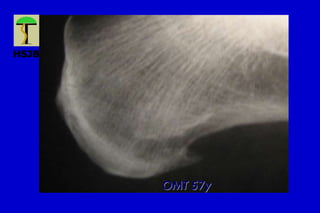

Talalgias

SC 60y

Incidencias radiológicas

OMT 57y